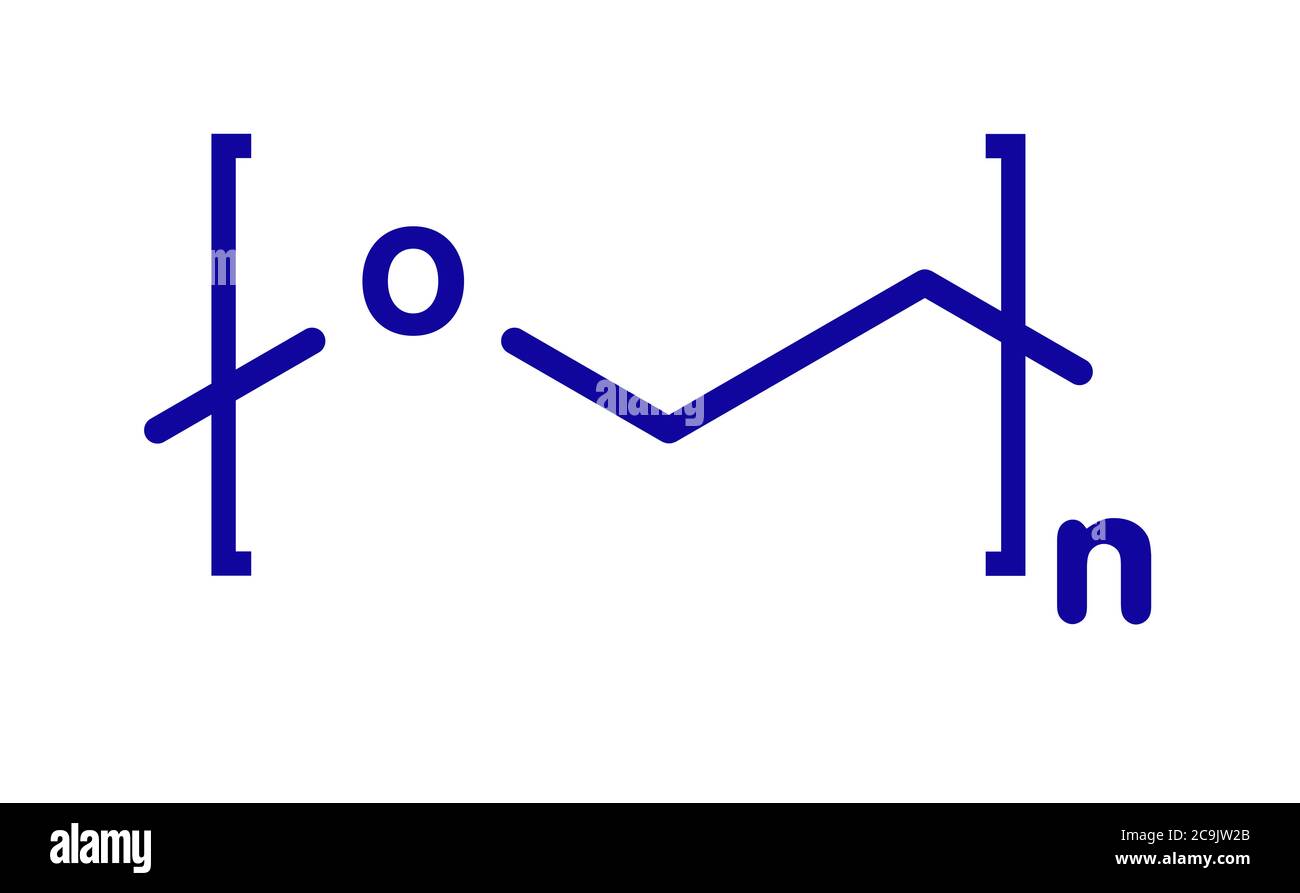

PEG 8 Ingredient INCIGuide

Poly thyl ne Glycol Ou PEG Ce Qu il Faut Savoir

Poly Ethylene Glycol PEG Based Hydrogels For Drug Delivery In Cancer

Poly thyl ne Glycol PEG Structure Chimique Les Formes De PEG Sont

Polyethylene Glycol PEG Concepts Applications And Side Effects